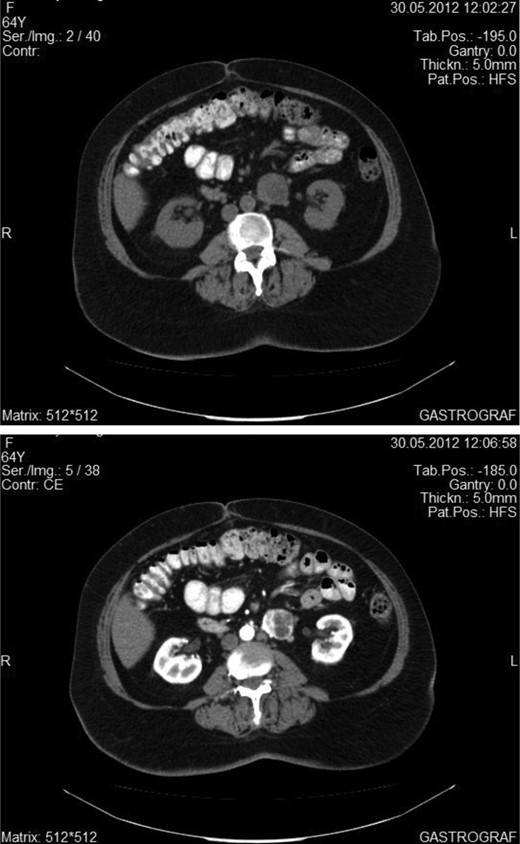

A 50-year-old woman was referred to our Clinic from a District Hospital to receive tertiary care due to an intra-abdominal mass. The patient suffered from vague abdominal pain, which began 3 months ago. At that time she underwent abdominal ultrasound that showed the existence of gallstone disease. For this reason, laparoscopic cholecystectomy was conducted. The patient was not relieved from her symptoms, seeking, soon after the operation, again medical care. Therefore, she underwent an abdominal CT scan, which showed the existence of a small (4 cm) retroperitoneal mass, adjacent to the left edge of the aorta, at the level of the lower pole of the left kidney. Under the diagnosis of para-aortic symptomatic tumor, the patient underwent a laparotomy, resulting in the total surgical excision of a highly vascular mass, which did not invade into the surrounding tissues. There was no evidence of tumors in other organs of the peritoneal cavity. During the operation and postoperatively, blood pressure was within the normal range. The dissected mass was soft, round shaped, dark brownish, well circumscribed, 4.5 × 3.2 × 2.8 cm in size. Immunohistochemistry showed intense expression of synaptophysin and chromogranin A and the index of cell proliferation Ki67 was ∼5%. It was diagnosed as an extra-adrenal paraganglioma. Her postoperative course was uneventful and the patient was discharged 6 days after the operation. An 18-month follow-up with abdominal CT scan at 1year postoperatively and the semi-annual clinical examination showed no evidence of recurrence (Figures 1 and 2).

Abdominal CT showing the enhancement of the tumor after intravenous administration of an iodine material.